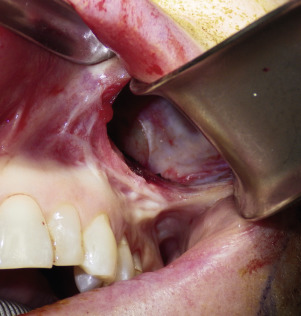

A 1-cm horizontal incision is made approximately 10–15 mm above the canine tooth. Using a radiowave or electrosurgery microneedle to incise the mucosa and soft tissues is hemostatic, and the incision is carried to the periosteal level of the canine fossa region ( Fig. 7.9 ). Alternatively, a vertical mucosal incision can be used but this approach provides less visual and working access compared with a horizontal entry. It is very common to see bleeding from the vascular rich mucosa and this is immediately cauterized with a small bipolar forceps to prevent bleeding throughout the case ( Fig. 7.10 ). The oral mucosa is very pliable, and even with a small incision, the surgical site can be well visualized when retracted. The incision continues to the periosteum and the entire dissection must remain subperiosteal. A Molt No.9 periosteal elevator is used to begin the subperiosteal dissection.

When beginning the subperiosteal dissection, it is not necessary to dissect medially to the pyriform (also spelled piriform) aperture (nasal region), because no part of the implant lies in this region in the average patient. The subperiosteal dissection is begun in the anterior maxillary region, and the initial dissection vector is superior, hence it is important to protect the infraorbital neurovascular bundle ( Fig. 7.11 ). The infraorbital nerve lies approximately 5–8 mm inferior to the infraorbital rim in line with the medial limbus ( Fig. 7.12 ). The implants are configured to lie inferior to the infraorbital nerve, and therefore aggressive infraorbital dissection is unnecessary.

After the anterior maxilla is dissected, the periosteal elevator is angled, and the remainder of the dissection is primarily in an oblique vector ( Fig. 7.13 ). All of the common implants extend over the lateral maxilla and zygomatic regions and taper out to a thin tail. This oblique vector of dissection is carried out over the malar region and extends over the medial portion of the zygomatic arch. It is extremely important to remember that the implant pocket should be just slightly larger than the intended implant ( Fig. 7.14 ). A grossly larger pocket only serves to encourage mobility and dead space. This is even more important if screw fixation is not being used, so the smaller pocket will retain the implant and reduce mobility.